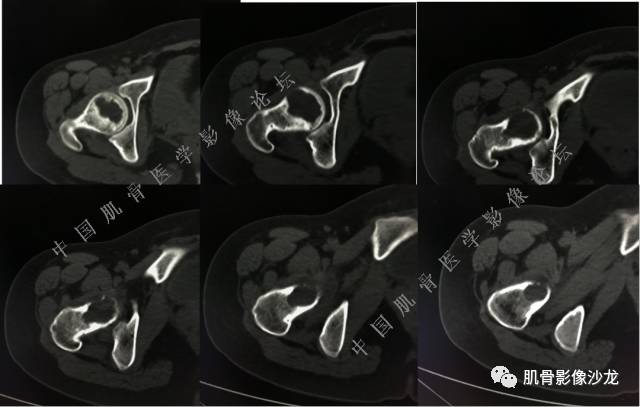

主诉:左髋疼痛1月余

现病史:患者1月余前无明显诱因出现左髋部疼痛,无明显活动受限,当地医院行X线检查,提示左股骨颈异常密度。遂来我院就诊。

既往史:曾患乙型肝炎,未正规治疗,目前无症状。

葛英霖 20:5 4 常规纤维类的多一些,冠状位没有看到明显脂肪。纤维结构不良、纤维组织细胞瘤、软粘纤之类。

夏威夷的风 20:55 大方向纤维类病变

Echo 20:55 考虑纤维类的依据是?

夏威夷的风 20:58 强化渐进性强化吧 边界清晰 里面也见线状低信号

飞鹰行动 21:01 良性纤维组织细胞瘤内部可以有少量脂肪

X(CT、MR)战警 21:01 泡沫细胞被吞噬后形成脂肪信号, bfh可以有脂肪条带样改变

Echo 21:04 总之这例就是各位老师说的硬化边明显,没有软组织肿块,没有侵犯,考虑良性病变,增强渐进性强化,所以考虑BFH